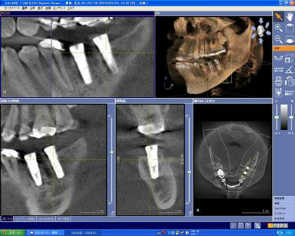

ポイント2 歯科用CTとCAD/CAMシステムの融合

当院では、歯科用CTを導入しております。

3Dで撮影した画像を、コンピュータでデータ処理することで、断層写真を得ることができる装置です。

歯科用CTでは、従来のレントゲンとは違い、骨の状態(質や厚み、高さ、形態など)を得ることができます。そのため、的確な位置、角度、深さにインプラントを埋入することができます。

しかもこの歯科用CTで撮影したデータを、最新のCAD/CAMシステムで設計・削り出しを行うことで、より精密で確実な人工歯を作製することができます。

ポイント3 ガイデッドサージェリー

歯科用CTで得た情報を基に、マウスピースに似た型(サージカルステント)を作製します。

このサージカルステントが、インプラントをより適切な位置・深さ・角度に埋入するための「ガイド」の役目をしています。

これをガイデッドサージェリーといいます。